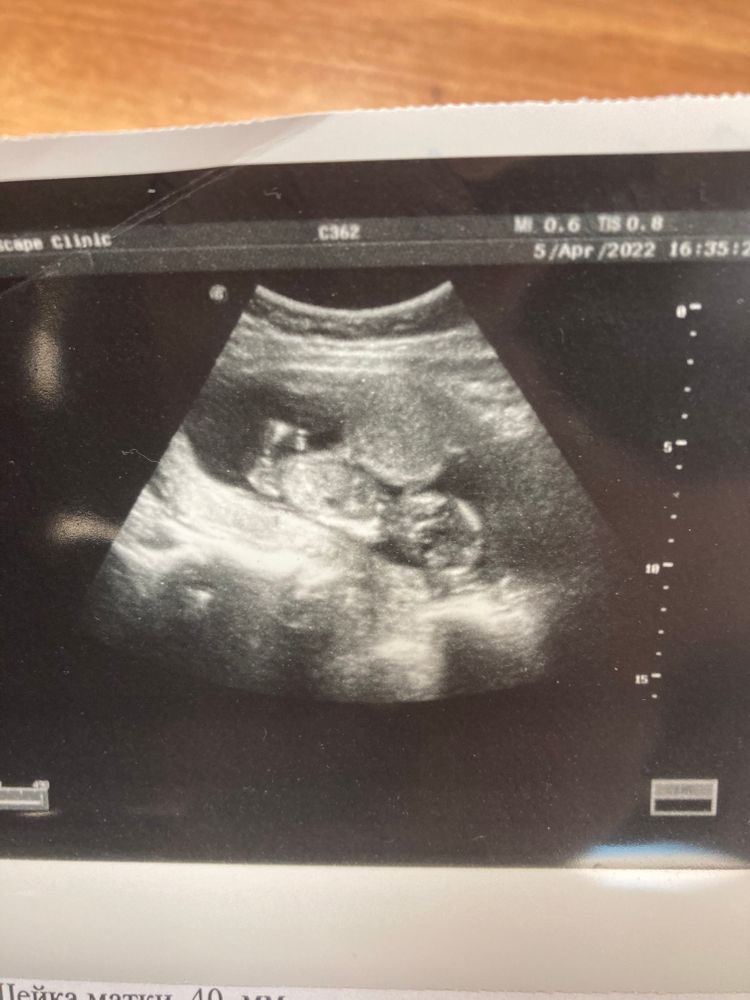

Как думаете видно пол?

Бугорка не видно, но я за девочку)

На девочку похоже, видны полосочки )

Marina , сегодня лучшего врача города прошла, сказали девочка🧸🌸🎀

Мне кажется девочка 💗 зернышко видно как будто😄

Дочка.

Мальчик

Я не разбираюсь как определить пол по снимку узи. Но первое о чем подумала, когда посмотротрела фото: Мальчик!

Настя, я тоже так подумала но пригляделась и вроде две половинки видно 😂🤭

Я не эксперт конечно, но мне кажется девочка🌷

Хотя посмотрела срок, уже даже не бугорок на узи виден, а половые органы. Ну по ощущениям и фотке, девочка

Пол малыша💐 Мы сходили на 2 скрининг.